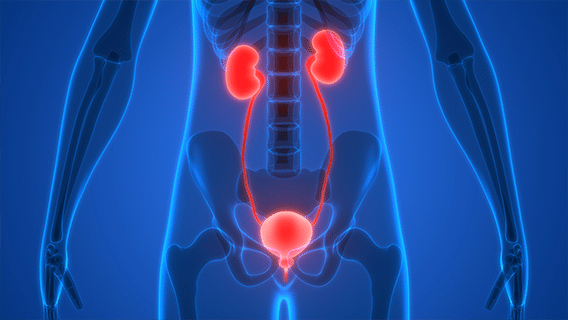

Рак верхних и нижних мочевыводящих путей — сложное онкологические заболевание, которое распространяется в почках и верхних мочевых путях. Рак мочевыводящих путей появляется в верхних мочевыводящих путях. К ним относят почечные чашечки, лоханки, а также мочеточники. Стенки данных органов выстланы несколькими слоями. К ним относятся слизистый, подслизистый, наружный соединительный и мышечный слои. Рак верхних мочевыводящих путей образуется непосредственно в поверхностном слизистом слое. Данный слой именуется уротелий, давая название заболеванию — уротелиальный рак верхних мочевыводящих путей.Читать далее